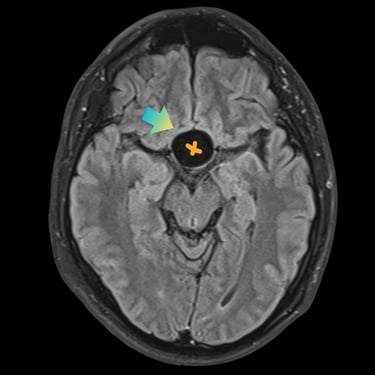

🧠Tumor selar quístico: abordaje mediante cirugía endoscópica transnasal (endoscopía selar).

Los tumores selares quísticos, como los adenomas hipofisarios quísticos o quistes de la bolsa de Rathke, pueden generar alteraciones visuales y hormonales. La cirugía endoscópica transnasal es una técnica mínimamente invasiva que permite el acceso seguro a la región selar, favoreciendo una resección eficaz con menor morbilidad.